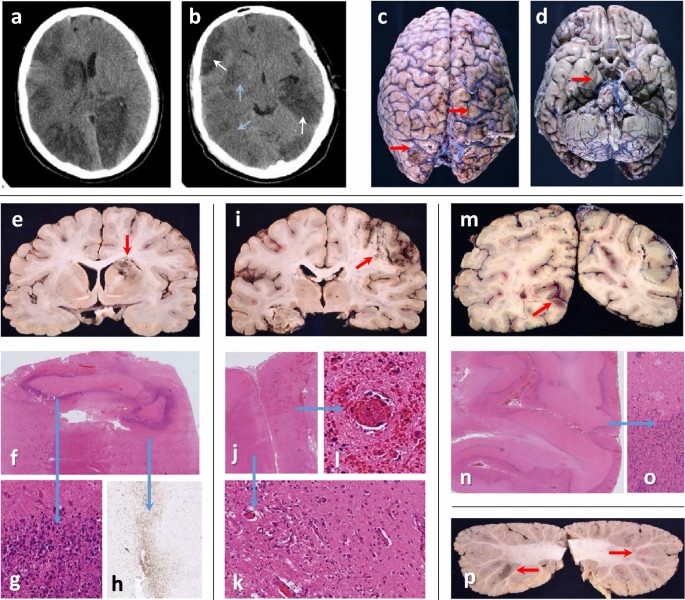

Its vascular nature means that when it gets into the lungs, it causes miniature blood clots (thrombus if only one and thrombi for many) in the lungs; when it gets into the heart, it causes lots of thrombi in the heart, when it gets into the liver, it causes thrombi in the liver, when it gets into the brain, it causes thrombi in the brain, and when it gets into the kidneys, it causes thrombi in the kidneys. All the images I linked to are from academic articles discussing Covid patients. For the lungs, I could have substituted my own CT scan–though I am not dead (yet), so I didn’t.